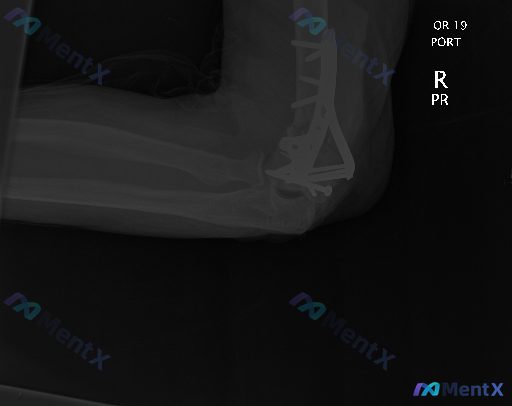

整理了一份右肘关节侧位X光片的资料,标注是「OR 19 PORT」(术后便携片)。

影像里能看到:

- 右肱骨远端有金属钢板和多枚螺钉固定

- 有金属伪影遮挡了部分骨骼细节

- 局部软组织密度看起来偏高

- 关节对位整体还可以

问题是:影像里说有“偏离正常”,但结合术后背景,大家第一眼会怎么区分哪些是术后预期改变,哪些是需要警惕的病理异常?

如果没有更多临床信息(比如术后多久、有没有疼痛发热),这份影像的下一步评估思路会是什么?